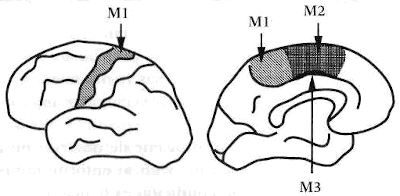

Figura 2-1. B = área de Broca; M = área motora; W = área de Wernicke. Los cuatro lóbulos figuran en la ilustración. Los críticos de Harlow postulaban que la lesión de Gage involucraba el área de Broca, o el área motora, o ambas, y usaron esta afirmación para atacar la idea de que había especialización funcional en el cerebro.

Gage tuvo daños graves en la zona ventromedial prefrontal, porción de un área que nuestras recientes investigaciones han definido como crucial para la toma de decisiones. (En la terminología neuroanatómica, la región orbital es conocida también como región ventromedial del lóbulo frontal y así me referiré a ella en el curso del libro. «Ventral» y «ventro-» derivan del latín venter, vientre, y esta región es el bajo vientre del lóbulo frontal, por decirlo así; «medial» designa la proximidad a la línea media, o superficie interna de una estructura). La reconstrucción de Gage reveló que ciertas zonas, que se consideran vitales para otros aspectos de la función neuropsicológica, no habían sido dañadas. Las capas corticales de la zona externa lateral del lóbulo frontal, por ejemplo, cuyo deterioro disminuye la capacidad de atención, de cálculo, o de cambio apropiado de un estímulo a otro, estaban intactas.

Esta investigación moderna autoriza ciertas conclusiones: Hanna Damasio y sus colegas podían afirmar con fundamento que la incapacidad de Gage para planificar su futuro, para conducirse de acuerdo con las normas sociales de comportamiento aprendidas previamente, y para decidir un curso de acción que en último término fuera ventajoso para su supervivencia, se debía a un daño selectivo de las capas corticales prefrontales de su cerebro. Ahora faltaba conocer el funcionamiento de la mente de Gage cuando se comportaba tan lamentablemente como lo hacía. Para conseguirlo, teníamos que investigar las modernas contrapartidas de Phineas Gage.